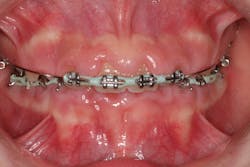

- 10% to 20% of the cases are typically attributed to calcium channel blockers, with nifedipine being the most notable problem (figures 4a and 4b).

Another laser that has been used to treat gingival enlargement and gummy smiles is a 9.3 micron CO2 laser (Solea from Convergent Dental; figure 2a). Unlike other lasers, the Solea laser has the capabilities of removing both soft and hard tissue, precise cutting accuracy due to control of both laser beam power and size, and the ability to cauterize inflamed tissue (figures 4c and 4d). Conventional instrumentation—such as blades, knives, and high-speed burs—can often lead to bleeding after surgical removal when the tissue is inflamed. With this type of CO2 laser, sutures and/or surgical dressing are often not needed.